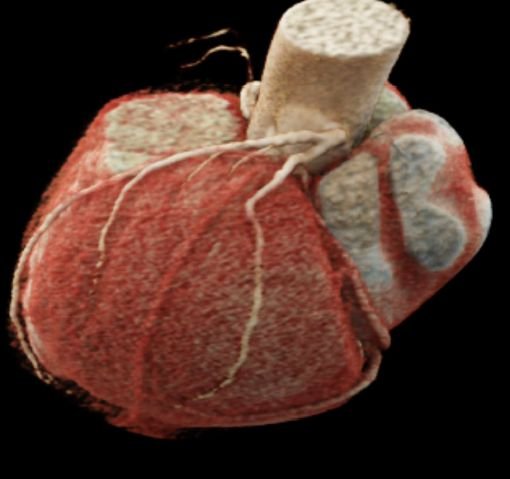

CT Cardiac Anatomy

CT Heart